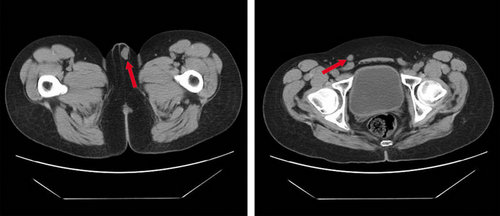

各种疝的ct影像诊断

图7 下腹部ct:左侧小睾丸,右侧腹股沟隐睾(箭头所示).